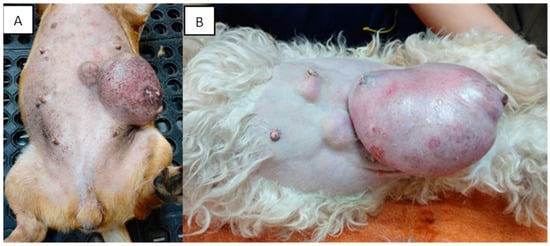

Mammary tumors are usually firm, well-defined nodules and their size can vary from millimeters to centimeters. They can occur in multiple glands at the same time and be of different histological types and grades. In addition, multiple tumors can coexist in the same mammary gland. The caudal abdominal glands are more frequently affected (up to 60% of cases) than the thoracic glands [130]. The skin in the affected area can be ulcerated or traumatized, as shown in Figure 2. Evaluation and palpation of regional lymph nodes are mandatory during diagnosis.

Figure 2.

Canines with multiple mammary tumors localized in different glands. Tumor measurements larger than 5 cm in diameter with inflammation (A) and ulcerated skin (A,B) can be seen (own photo).